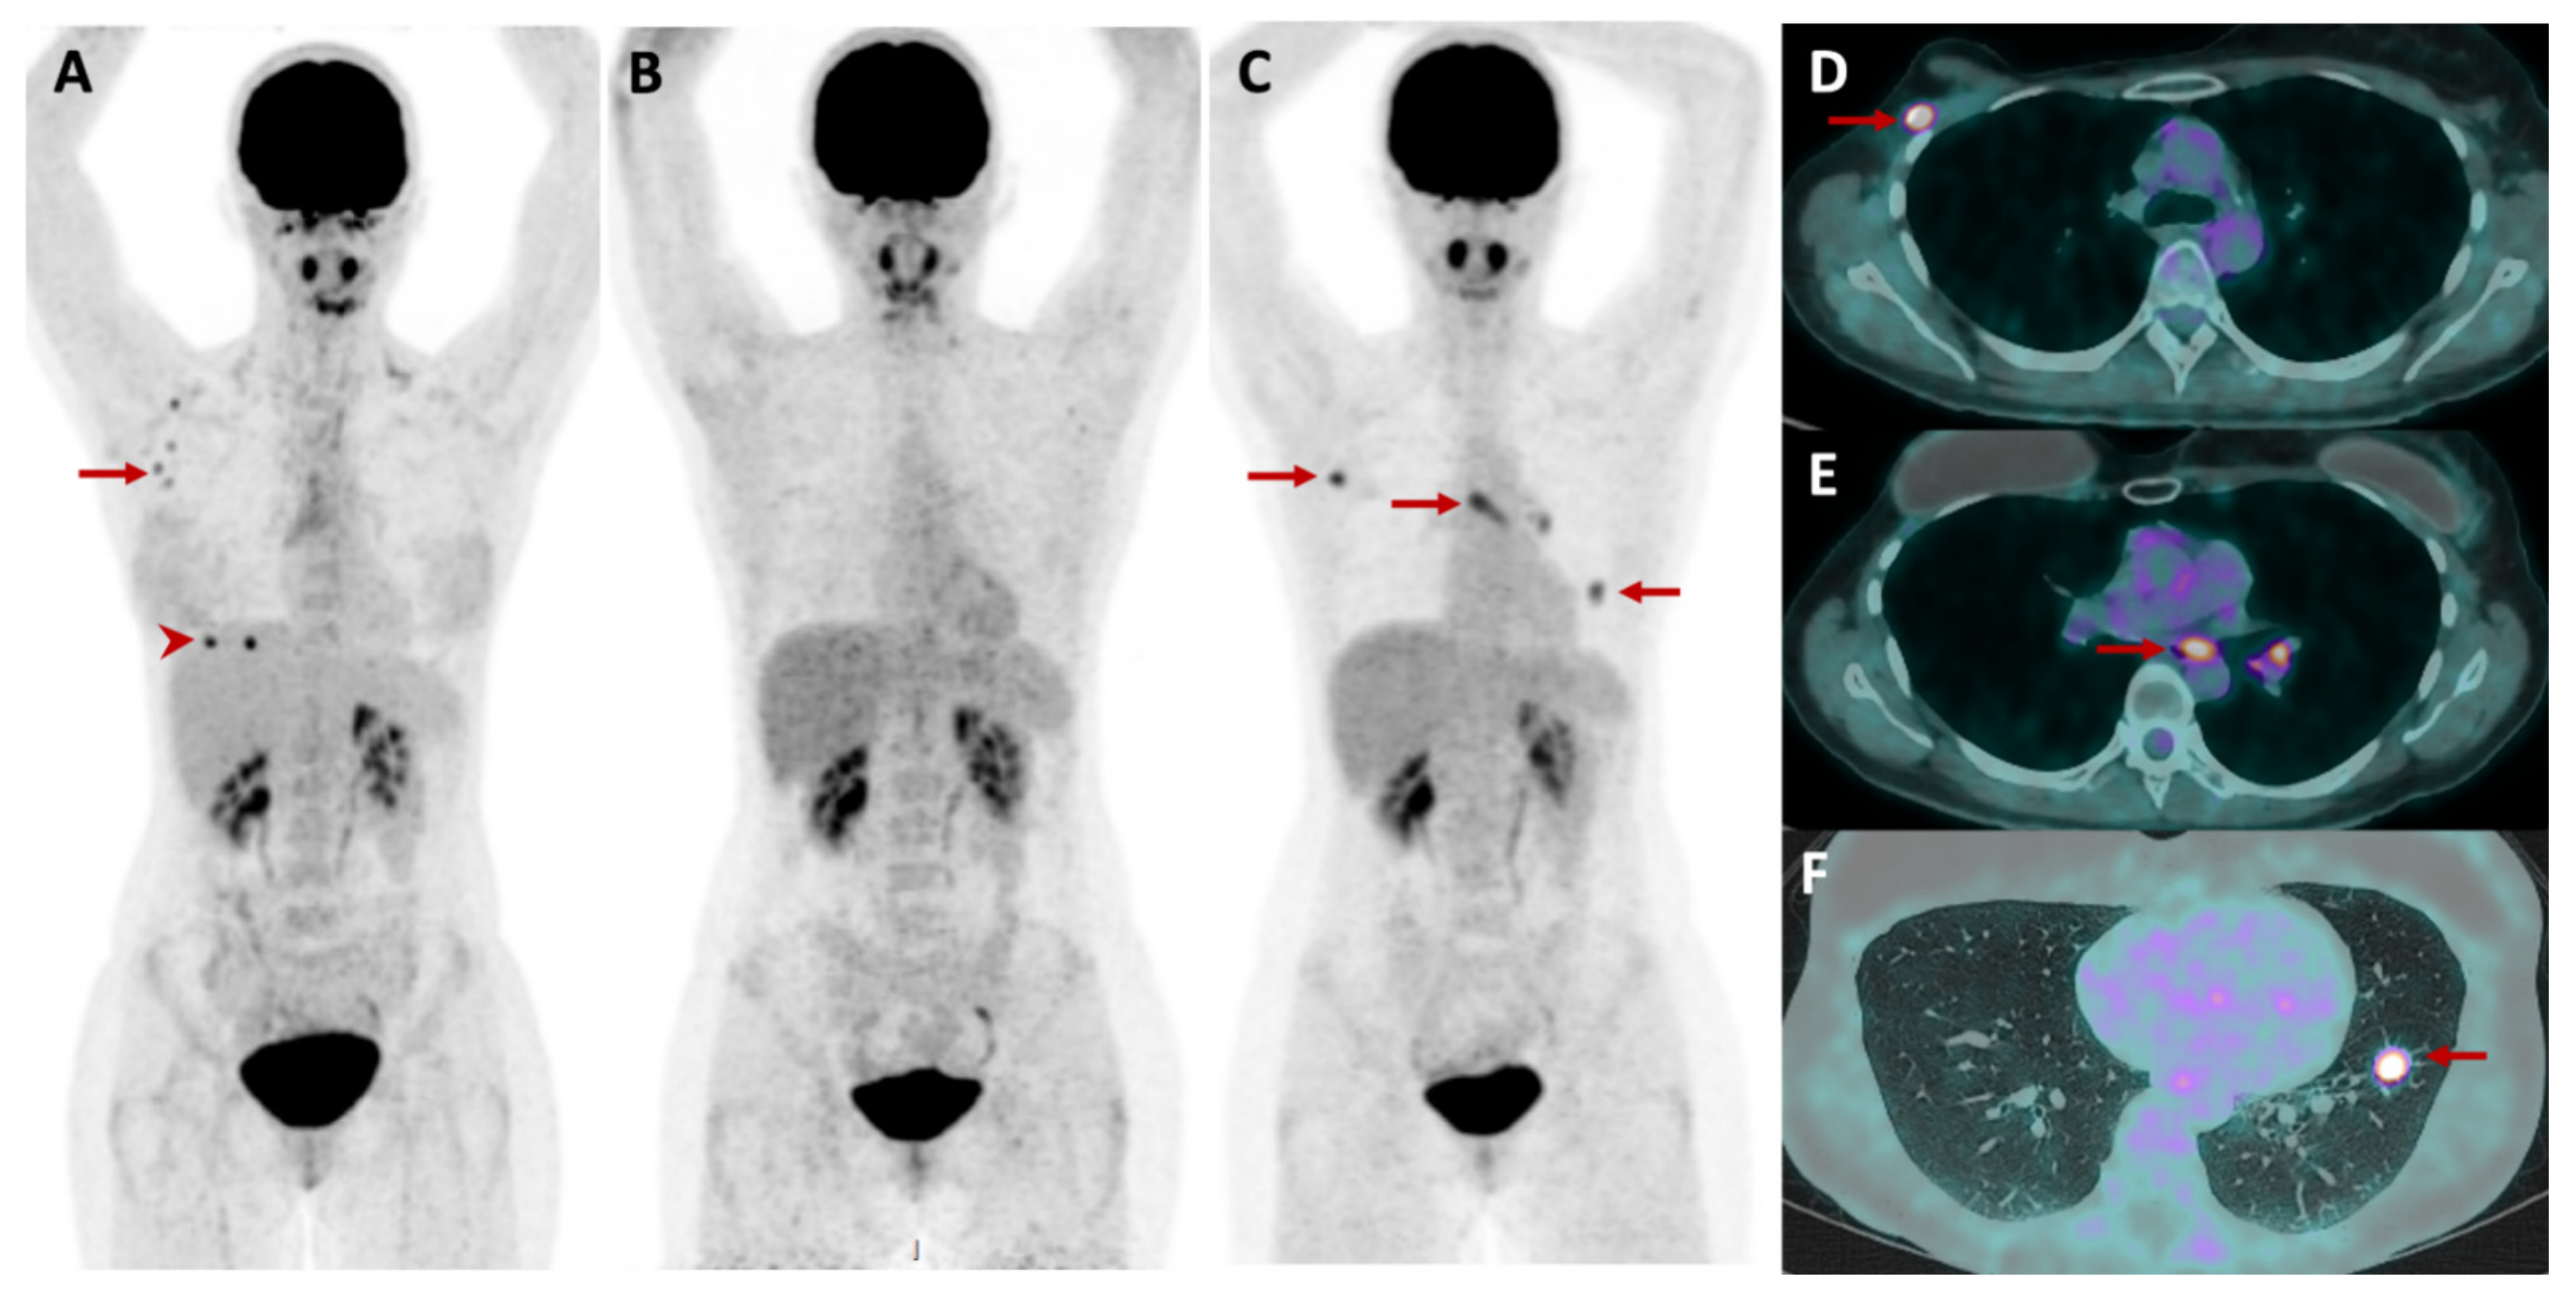

2.5.3. Metabolic and Receptor-Specific Imaging

2.5.4. Combined Modalities

4.4. Prostate Cancer